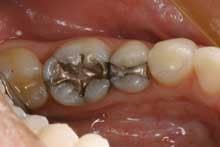

Another clinical example is this 35-year-old woman (Figure 3).

Tooth No. 19 has a large amalgam and fractures present in the lingual groove and the distal marginal ridge. Tooth No. 20 has a conservative amalgam restoration with a small area of recurrent decay present under the distal margin. When presenting the treatment plan to the patient, she is shown this picture. We explain to her the reasons we are recommending a crown with a build-up on tooth No. 19 and that the presence of the existing fracture lines put the distal lingual cusp at risk. We also explain to the patient that tooth No. 20 will require a new composite filling to replace the old amalgam restoration that is beginning to fail. We then explain the benefits of doing both restorations at the same time. Her response was, "I definitely want to do both at the same time. It's too hard for me to get time off from work to come to the dentist."